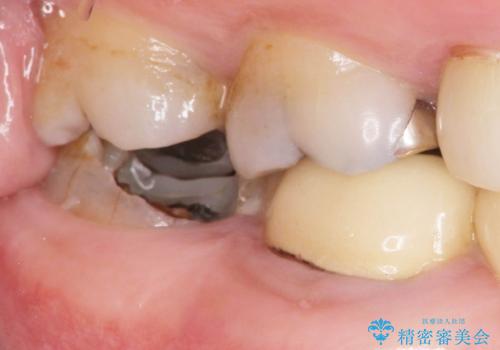

壊れてしまったインレーおよび、虫歯を神経を温存できるよう丁寧に除去したのち、耐破折に優れるセラミッククラウンで再補綴治療を行います。

再発した虫歯は小さくなかったものの、丁寧に虫歯をとることで神経を温存することができました。